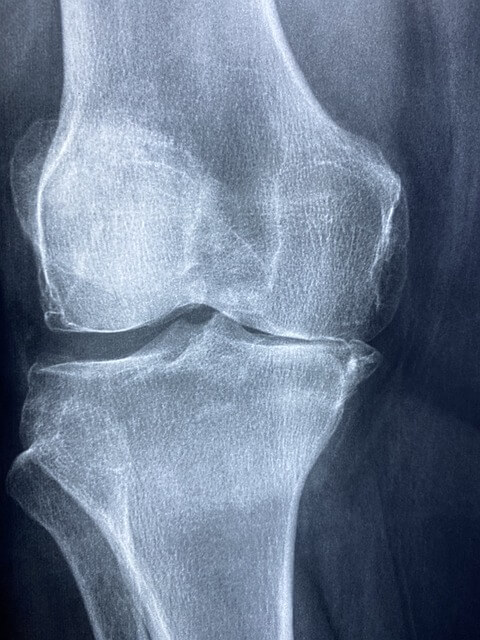

- 심한 관절염 환자

무릎 연골이 거의 소실된 말기 관절염 환자의 경우, 무릎 연골주사의 효과가 제한적일 수 있습니다. 이 단계에서는 주사치료보다는 인공관절 치환술과 같은 수술적 치료가 더 적합할 수 있습니다.